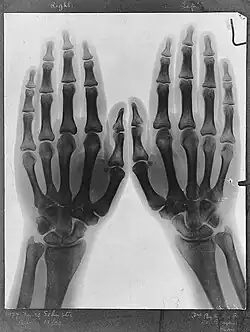

Sir Franz Arthur Friedrich Schuster (12 September 1851 – 14 October 1934) was a German-born British physicist known for his work in spectroscopy, electrochemistry, optics, X-radiography and the application of harmonic analysis to physics. Schuster's integral is named after him.[2] He contributed to making the University of Manchester a centre for the study of physics.[3][4]